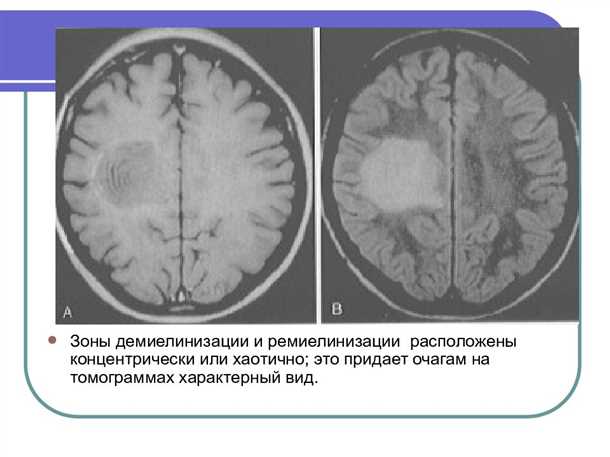

Диагностика поражений миелиновой оболочки основана на комплексном подходе, который включает в себя клинический осмотр, лабораторные анализы, инструментальные исследования и генетическую диагностику. Врачи обращают внимание на характерные симптомы, такие как изменение в двигательной активности, нарушение координации движений и повышенная утомляемость. Кроме того, проводятся исследования жидкости спинномозгового канала, молекулярно-генетические анализы, магнитно-резонансная томография и другие инструментальные методы.

- Инструментальные методы диагностики, такие как магнитно-резонансная томография и электроэнцефалография, для визуализации изменений в структуре и функции мозга;